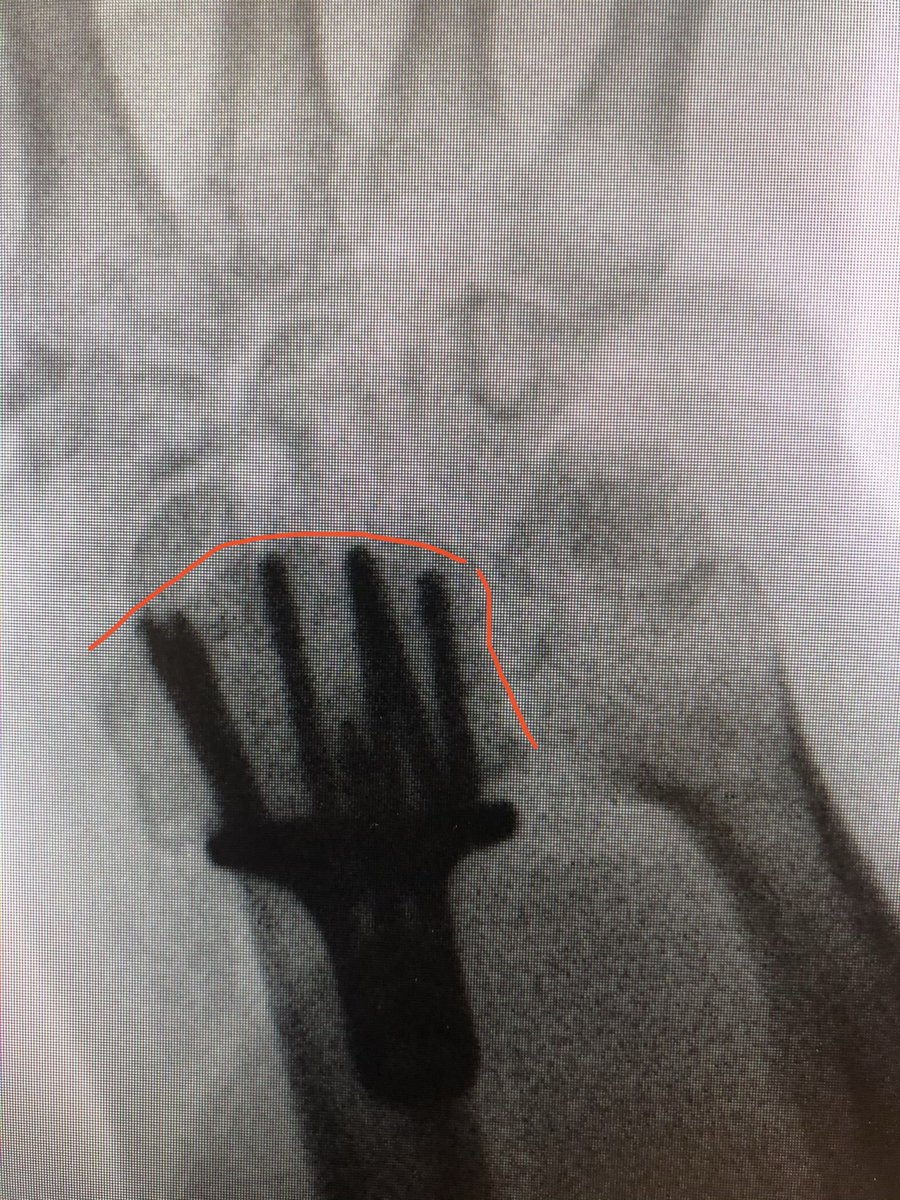

Simple everyday distal radius fracture. 60 yr old nurse. Medically well. #OrthoTwitter

I see conventionally this would be called an ‘extra-articular’ fracture.

Do we oversimplify this? Isn’t DRUJ a ‘joint’?

Isn’t the distal ulna getting all into the business of the carpals a ‘joint disruption’?

I would fix this.